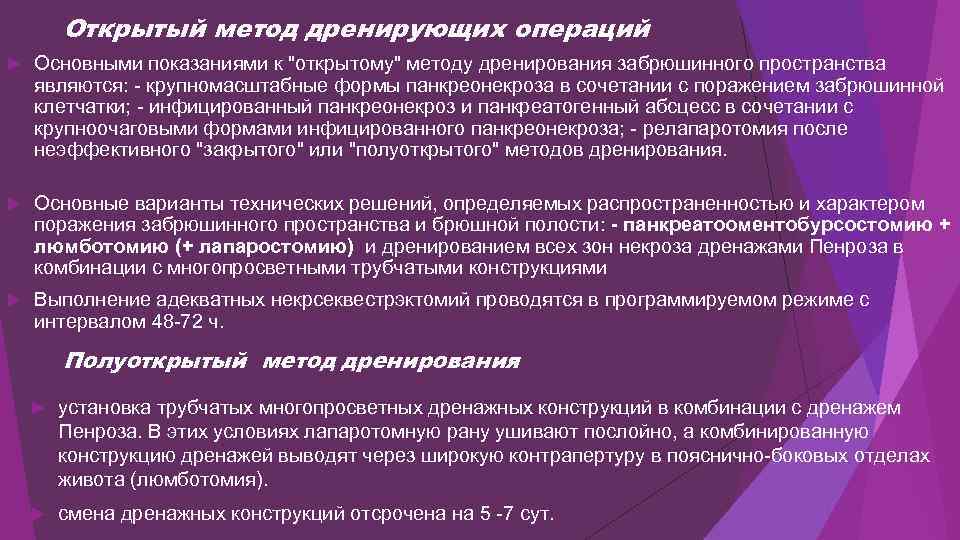

Острая блокада терминального отдела холедоха (острый панкреатит)

Острая блокада терминального отдела холедоха (острый панкреатит)